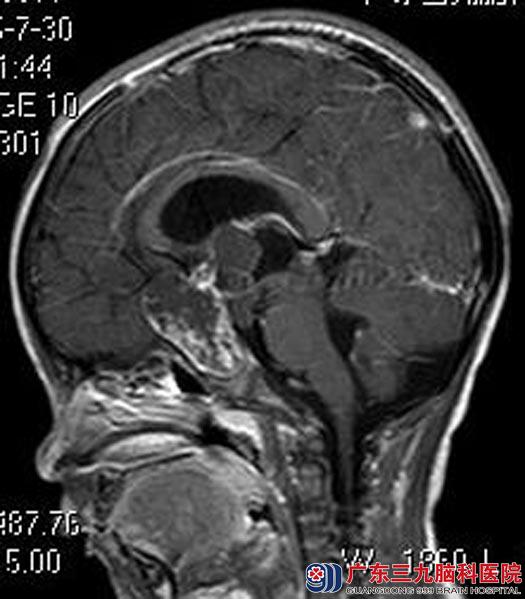

住院在综合神经外科,头颅MR检查提示:鞍区(鞍上为主)示一团块状异常信号影,大小约42.6mm×33.2mm×52.7mm,考虑颅咽管瘤可能性大;左侧大脑半球、左侧基底节区、右侧丘脑及胼胝体多发病变,考虑脑梗塞可能。